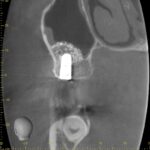

レントゲンは70代男性。本日、無事にインプラント上にジルコニアの歯が入った。サイナスリフトをラテラルスリット法でおこない、骨造成をし、インプラント治療をやらせていただいた。

サイナスリフト法インプラント治療は骨の厚みがなくインプラント治療をあきらめざるを得なかった患者さんにもとても有効な術式である。しかもラテラルスリット法は従来より侵襲や術後の腫れが少ない手術法である。